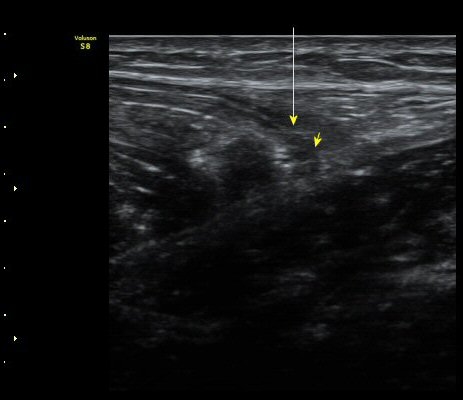

ÃÊÀ½ÆÄ °Ë»ç

¼ö»ó ÈÄ 2ÀÏ Â°

³»Ãø ºñº¹±Ù Á¾´Ü¸é°Ë»ç¿¡¼­ ±ÙÀ°°ú ÈûÁÙ ÀÌÇà ºÎÀ§¿¡ ÀÛÀº ÆÄ¿­°ú ¼ö¾× Àú·ù, ÆÄ¿­ µÈ

±ÙÀ°ÀÇ ±ÙÀ§ºÎ·Î ´ç°ÜÁüÀÌ °üÂû µÊ(±×¸² 1, 2, 3).